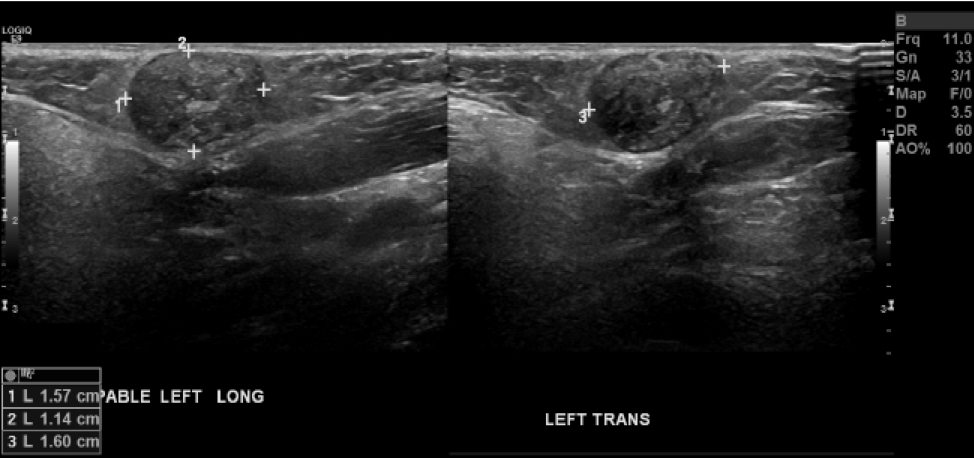

Diagnostic tests. Ultrasonography of the neck was ordered, the results of which showed a spherical, subcutaneous, solid, hypovascular mass measuring 1.6 × 1.1 × 1.6 cm (Figure 1).

Figure 1. Ultrasonogram of the neck showed a spherical, subcutaneous, solid, hypovascular mass measuring 1.6 × 1.1 × 1.6 cm.